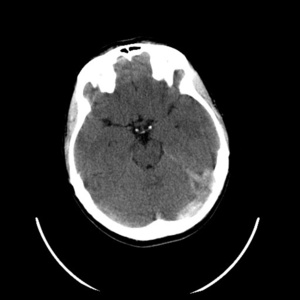

Rutynowa tomografia komputerowa bez środka cieniującego w 20% przypadkach pozwala stwierdzić hiperintensywne skrzepliny w rzucie zatok lub żył mózgowia (dense clot sign) (ryc. 1). W przypadku zakrzepicy żył korowych niekiedy widoczny jest tzw. objaw struny (czyli linijna, hiperintensywna zmiana odpowiadająca zakrzepowi w świetle naczynia żylnego). Pośrednim objawem CVT są cechy obrzęku mózgu (np. spłycenie bruzd, zwężenie układu komorowego, obserwowano w 20-50% przypadków). Charakterystyczna dla udaru żylnego jest lokalizacja ogniska naczyniopochodnego (zarówno niedokrwiennego, jak i krwotocznego) nie odpowiadająca zakresowi unaczynienia tętnic mózgowych, oraz liczne izolowane ogniska położone podkorowo z zaoszczędzeniem kory mózgu.11 Zakrzepica zatoki prostej zwykle upośledza drenaż żylny na dużym odcinku, co skutkuje zmianami zlokalizowanymi w rejonie parasagitalnym (ryc. 2A, B). Zakrzepica żyły zespalającej dolnej (żyła Labbego) prowadzi do zmian w płacie skroniowym. Zakrzepica żył głębokich mózgu powoduje jednostronne lub obustronne zmiany we wzgórzach, jądrach podstawy i torebce wewnętrznej.11W około 30-40% przypadków CVT towarzyszą ogniska krwotoczne. Zgodnie ze stanowiskiem ekspertów American Heart Association (AHA) i American Stroke Association (ASA) w przypadkach krwotoków płatowych o niejasnej etiologii i (lub) lokalizacji nieodpowiadajęcej zakresowi unaczynienia tętniczego, należy brać pod uwagę możliwość CVT.4,11